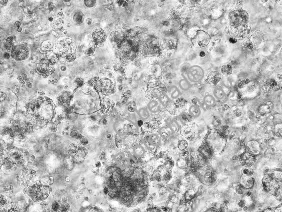

在肿瘤相关领域,赛箔与合作者共同研发基于生物3D打印技术构建的肿瘤微组织(PDT),涵盖十余个癌种,包括高发肿瘤、难治肿瘤、妇科肿瘤和儿童肿瘤,培养成功率超过了90%。通过近千例样本研究,证实PDT与患者组织具有高度一致的分子特征和药物敏感性,1-2周即可获得准确的药敏检测结果,为治疗赢取宝贵时间,并且可为新药研发企业提供药效评价、入组标准建立、适应症筛选等服务。在再生相关领域,赛箔已建立多种3D组织工程皮肤,包括表皮模型、全层皮肤模型、黑素皮肤模型等,并相应开发多种体外功效测试方法。